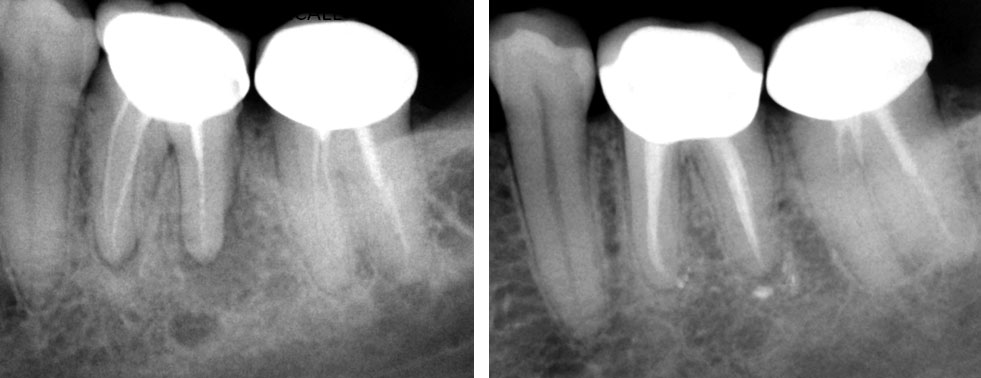

Clinical Case

Broken instrument in the mesio-buccal root of the maxillary second molar.

Pre-op

Residual caries seen after temp removal.

After caries removal

Cotton pellets placed over the palatal and Disto-buccal orifices to prevent the instrument from slipping into those canals.

Fractured instrument in mesio-buccal canal

Fractured instrument removed with ultrasonics

Canals cleaned, shaped and obturated

Fiberglass-post and composite core placed

Post-op

Pre-op & Post-op